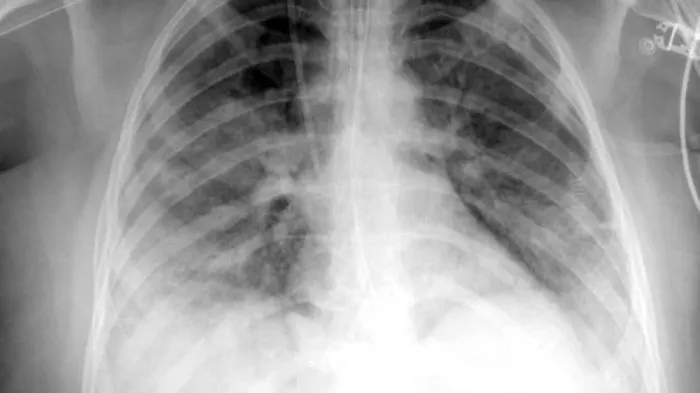

兩者的涵義一樣,意指患者雖然處於缺氧狀態(SpO2<95%),但臨床症狀卻不明顯,沒有喘、呼吸加速等症狀。也因為症狀不明顯,肺炎嚴重度容易被低估,等到更進一步惡化的時候,醫療端很可能措手不及。所以近期才有不少患者喘起來時,胸部X光片已經雙側發白,雖然緊急插管但最終仍不治的遺憾新聞。